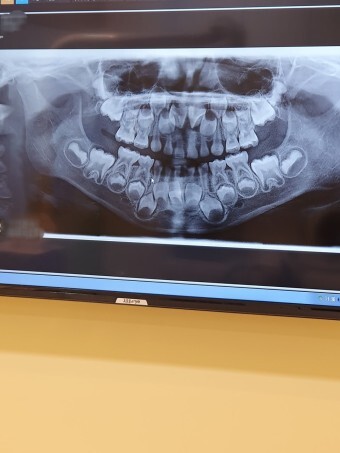

치아는 소화기의 한 기관으로 구강내에서 상악골과 하악골의 치조돌기에 식립되어있는 고도로 석회화된 경조직성 기관이다. 치아는 동물의 종류에 따라서 7개월경부터 20~30개월까지 맹출하는 치아를 유치라고 하며 만 6세부터 21세까지 맹출하는 치아를 영구치라 한다.

태생 16주 경에는 유치치배의 설측에 영구치 치배도 형성되어 유치의 치배 발육과 동일하나 과정으로 성장을 해 나간다. 태생 18주가 되면 치아의 경조직이 형성되기 시작하고 치아의 경조직 중에서 상아질이 형성되고 곧이어 법랑질의 형성이 시작되는데 이때 법랑질에서 기질이 형성되면 곧 치아의 석회화기 일어난다. 상아질과 법랑질이 법랑질과 백악질의 경계부에 도달하면 치근의 상아질이 형성되기 시작하고 이어서 백악질, 치조골 치주인대의 형성이 시작된다.

6.맹출

치관의 형성이 완료되고 치근이 형성될 무렵 치아의 주위에 있는 연조직과 치관을 덮고 있는 골질을 흡수하면서 구강을 향하여 이동을 시작한다. 치아의 맹출이 시작되는 시기는 치근의 형성이 시작되는 시가와 대략 비슷하며 치근이 완성되는 것은 치아가 맹출하고 난 뒤 1~2년 후이다. 치근끝이 만들어졌을 때 치아셩성이 완성되었다고 한다. 치아의 후에도 치아의 맹출은 교합면쪽으로 평생 계속된다.

치수강은 나이가 듦에 따라 점점 좁아지고 유치의 경우에도 치아우식증이나 교모로 인한 자극의 결과로 수실에 이차상아질이 생겨 수실이 좁아지기도 한다. 유치의 탈락은 파치세포가 나타나서 유치의 치근을 흡수하여 치주인대와의 결합이 느슨해지면서 일어나고 이어서 영구치와의 교환이 이루어진다.